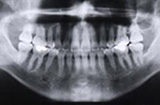

3.レントゲン検査

歯の並びや形・距離を分析

- レントゲンで検査を行い、歯の歯周組織から歯槽骨を詳細に診断。適切な歯列移動を行えるようにアプローチします。